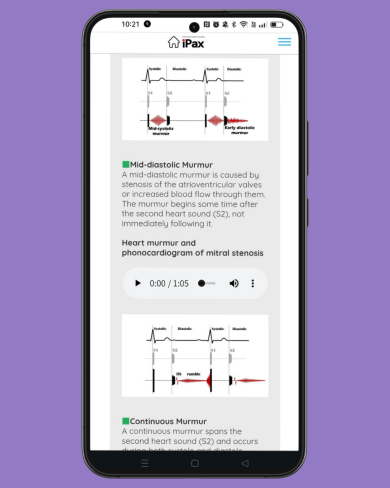

On June 21, the quiz focuses on diastolic murmurs. Please listen carefully and distinguish between the three types of heart murmurs. (June 21, 2025)